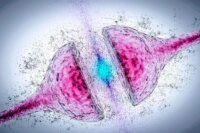

New Parkinson’s Drug Targets Disease at Genetic Level

Summary of Breakthrough Parkinson’s Drug Targets Disease at Its Genetic Roots: A new experimental treatment, BIIB094, targeting the LRRK2 gene, shows promise in lowering LRRK2 protein levels in a clinical…